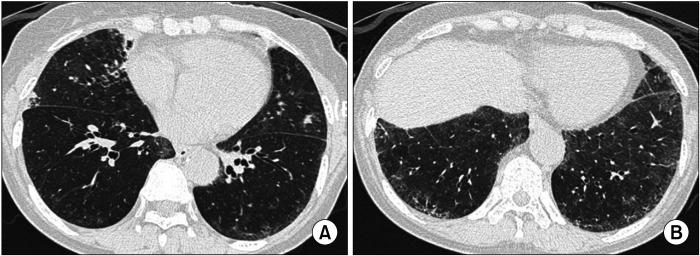

Interstitial lung disease (ILD) is often observed in connective tissue diseases (CTDs), frequently in rheumatoid arthritis, systemic sclerosis, primary Sjögren's syndrome, and inflammatory myositis. Early detection of ILDs secondary to rheumatic diseases is important as timely initiation of proper management affects the prognosis. Among many imaging modalities, high-resuloution computed tomography (HRCT) serves the gold standard for finding early lung inflammatory and fibrotic changes as well as monitoring afterwards because of its superior spatial resolution. Additionally, lung ultrasound (LUS) and magnetic resonance imaging (MRI) are the rising free-radiation imaging tools that can get images of lungs of CTD-ILD. In this review article, we present the subtypes of ILD images found in each CTD acquired by HRCT as well as some images taken by LUS and MRI with comparative HRCT scans. It is expected that this discussion would be helpful in discussing recent advances in imaging modalities for CTD-ILD and raising critical points for diagnosis and tracing of the images from the perspective of rheumatologists.

间质性肺疾病(ILD)常在结缔组织病(CTD)中出现,常见于类风湿关节炎、系统性硬化症、原发性干燥综合征和炎性肌病。早期发现风湿性疾病继发的ILD很重要,因为及时开始适当治疗会影响预后。在众多成像方式中,高分辨率计算机断层扫描(HRCT)因其卓越的空间分辨率,是发现早期肺部炎症和纤维化改变以及后续监测的金标准。此外,肺部超声(LUS)和磁共振成像(MRI)是新兴的无辐射成像工具,能够获取CTD-ILD患者肺部的图像。在这篇综述文章中,我们展示了通过HRCT在每种CTD中发现的ILD图像亚型,以及一些LUS和MRI拍摄的图像,并与HRCT扫描进行对比。期望这一讨论有助于探讨CTD-ILD成像方式的最新进展,并从风湿病学家的角度提出图像诊断和追踪的关键点。